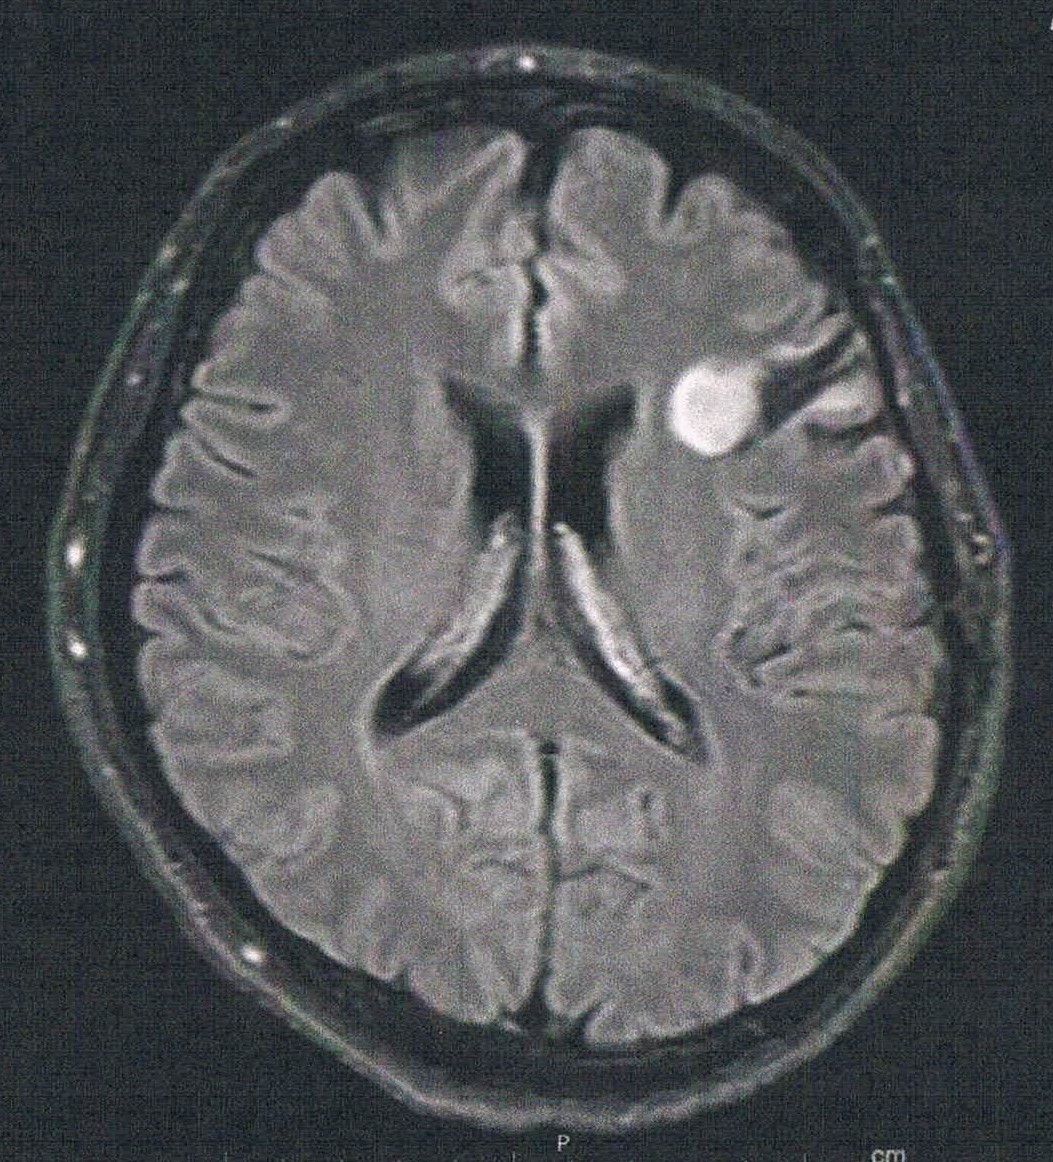

手術から8.0年が経過した。半年ごとの定期検査です。

- 悪性転化しやすい腫瘍の種類(びまん性星細胞腫グレード2)

- 造影剤を注射してMRI検査

- 年レベルでおおきくなっている

- 手術して取りに行く